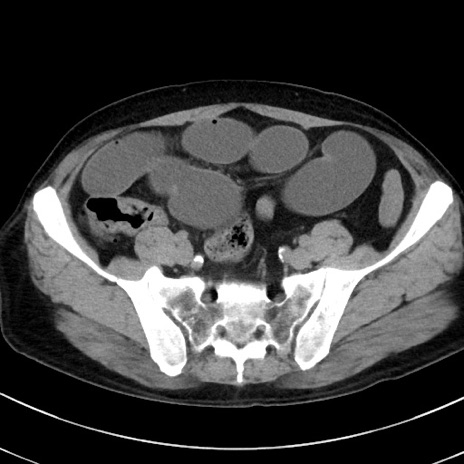

症例38(横断像)

【症例】70歳代 男性

【主訴】腹痛・嘔吐

【現病歴】昨晩より、嘔吐・腹痛あり。今朝になっても嘔吐あり。来院。

【既往歴】心臓バイパス手術、開腹胆摘、腸閉塞

【身体所見】BP 107/71mmHg、HR 116/min、腹部:平坦、軟、下腹部に軽度圧痛あり。反跳痛なし。

【データ】WBC 15100、CRP 0.32